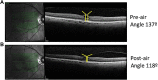

Methods: We conducted a retrospective consecutive case series of 20 eyes from 19 individuals with focal VMT who underwent pneumatic vitreolysis with intravitreal air (January 2017 to November 2018). We analyzed patients via spectral-domain optical coherence tomography before intravitreal air injection and at 1 month. The primary outcome measure was release of VMT.

Results: We observed release of VMT in 55% of individuals. An analysis limited to phakic eyes demonstrated release of VMT in 69%, and 65% developed improved best-corrected visual acuity. Individuals with persistent VMT and visual improvement had a significant reduction in angle of vitreoretinal insertion (P < .01), area under VMT (P < .05), and subfoveal cyst area (P < .05).

Conclusions: Intravitreal air is an effective treatment for focal VMT. In individuals with persistent VMT, visual-acuity improvement was associated with a reduction in overall VMT.